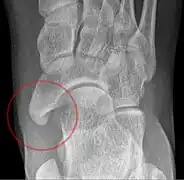

Cornuate navicular bone